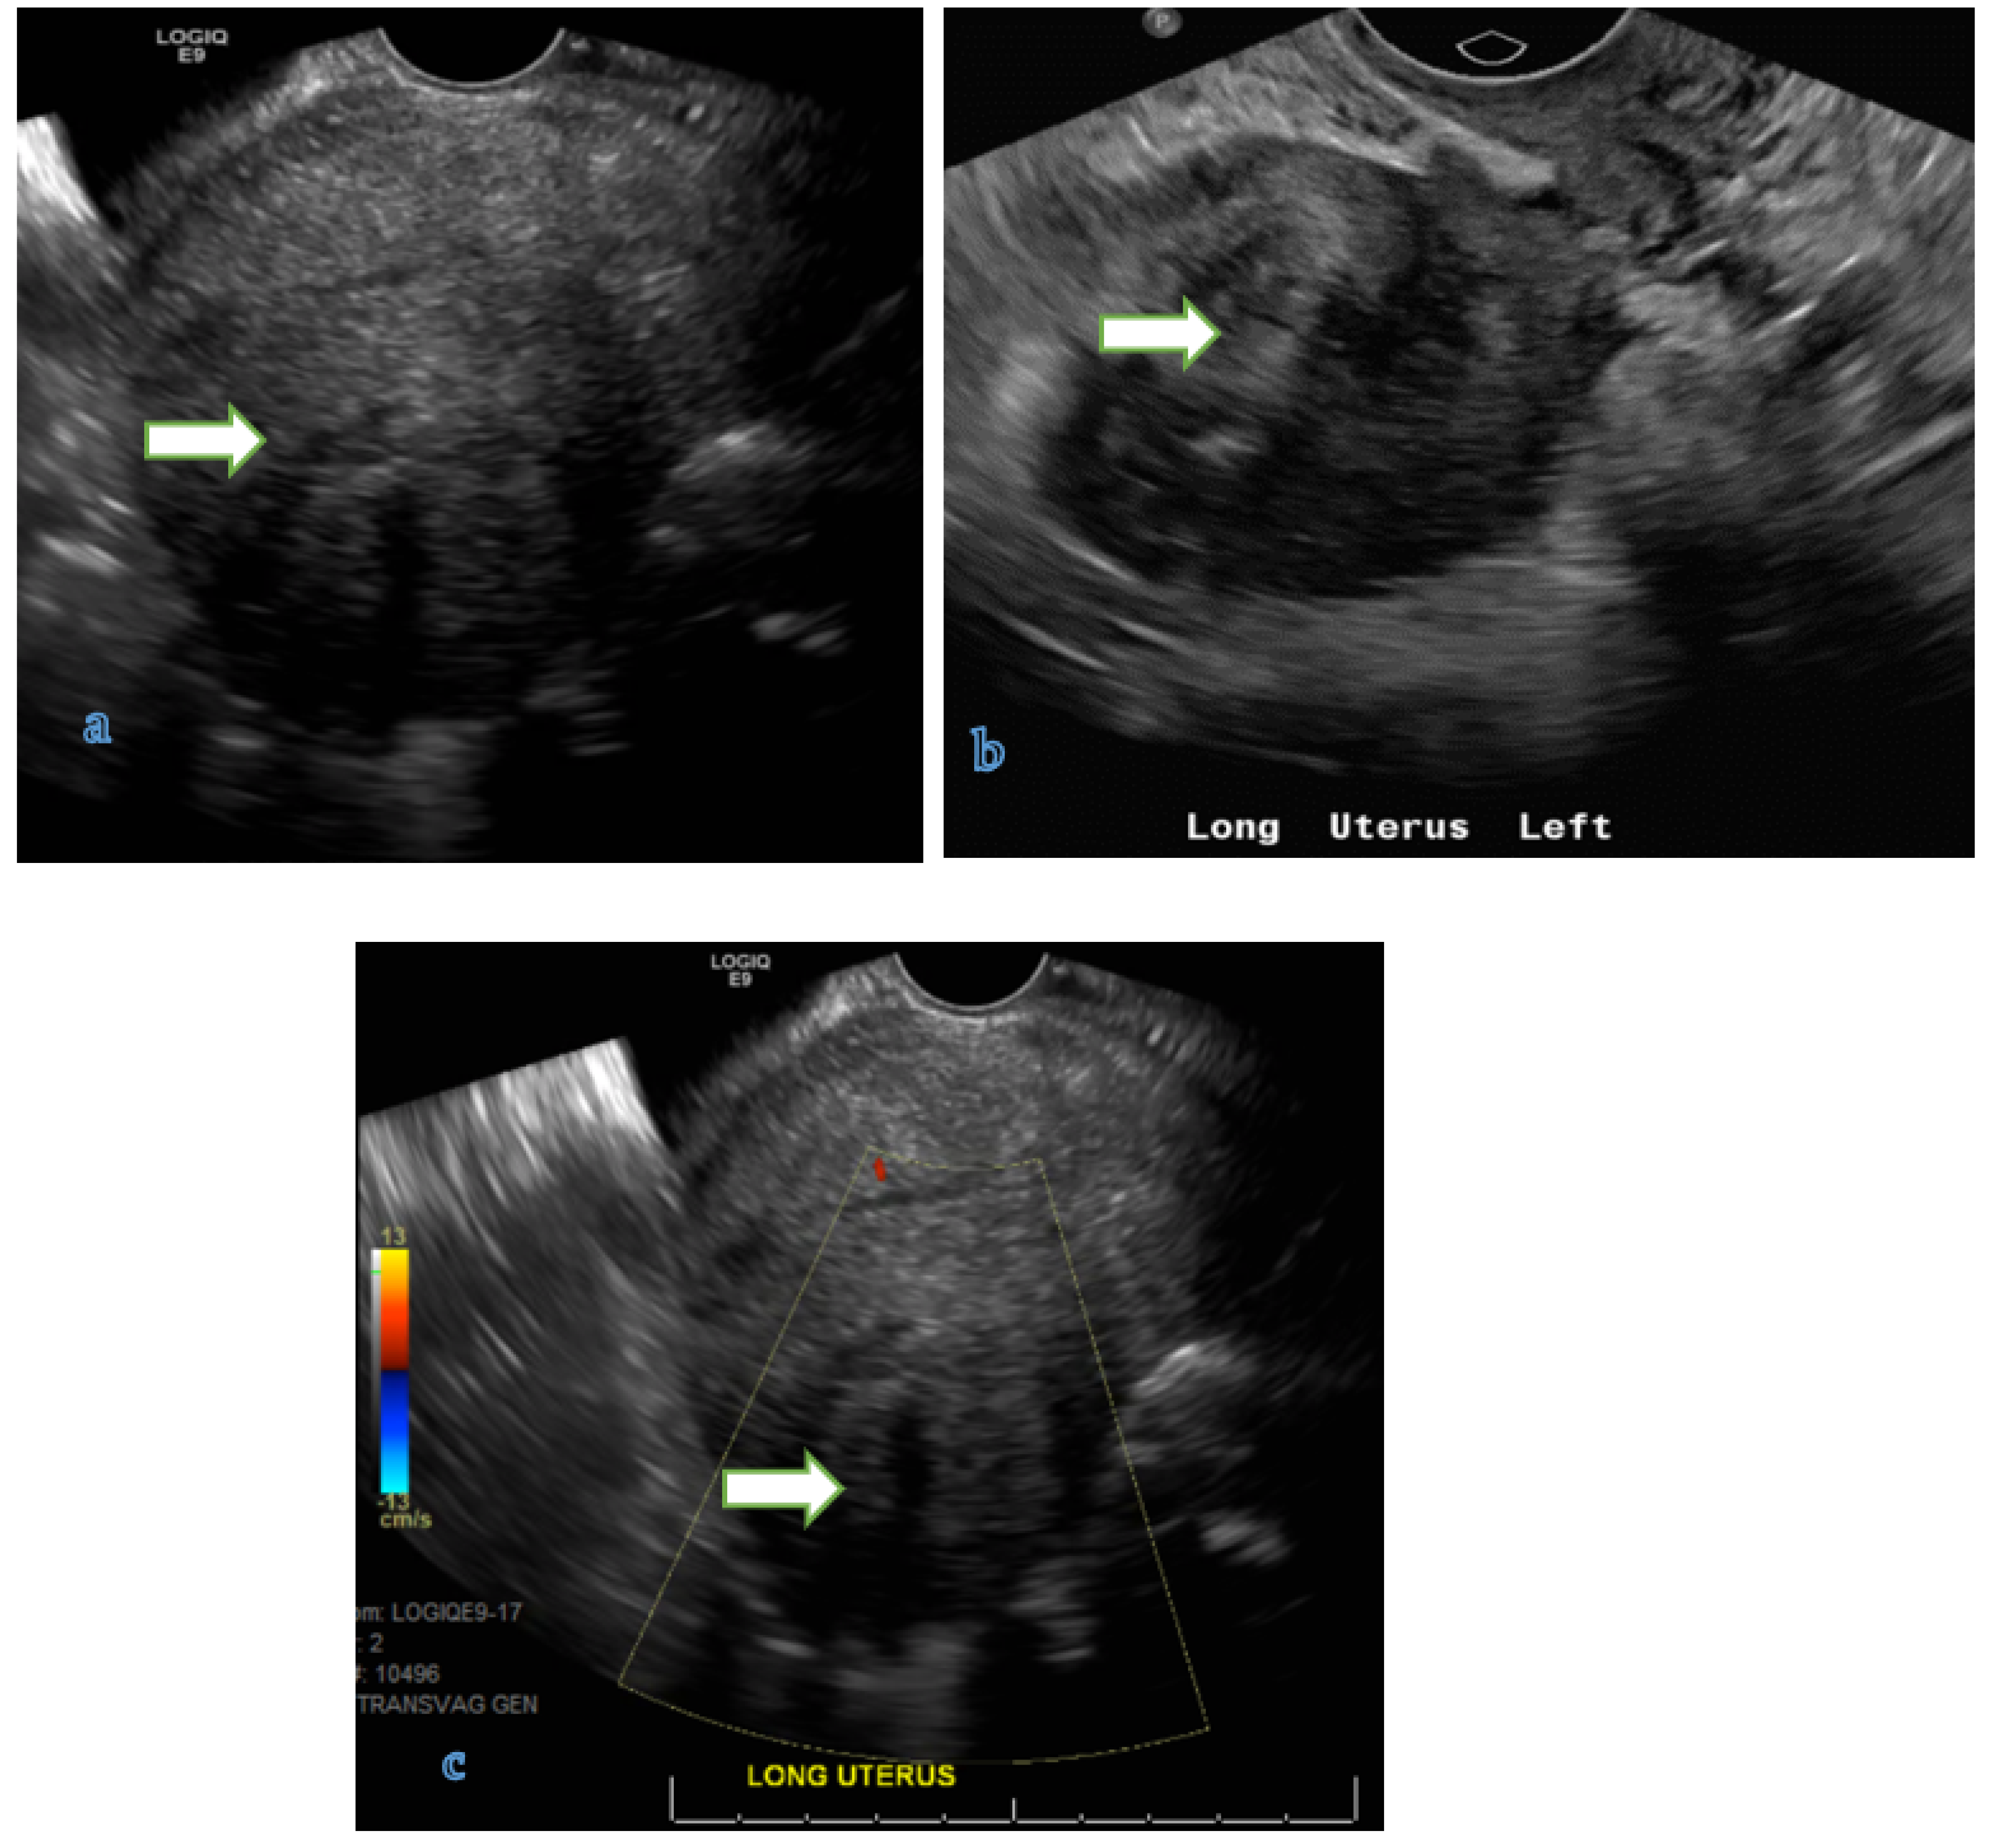

4.1. Ultrasound

| O-RADS Score | Risk Category | Lexicon Descriptors | Management | ||||

| Typical dermoid cyst <10 cm (Figure 2) | Follow up in 8–12 weeks | US specialist, gynecologist management or MRI | |||||

| Typical endometrioma <10 cm | Follow up in 8–12 weeks | US specialist, gynecologist management or MRI | |||||

| 3 | Low risk of malignancy (1% to less than 10%) | Unilocular cyst ≥ 10 cm (simple or non-simple) | US specialist or MRI Gynecologist management | ||||

| Mutlilocular cyst < 10 cm with smooth inner wall, CS = 1–3 | |||||||

| Solid smooth (regardless its size), CS = 1 | |||||||